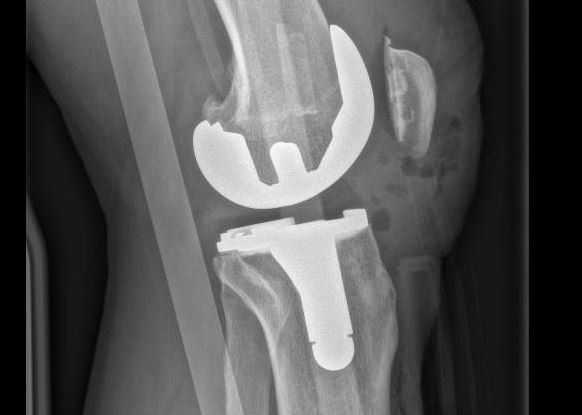

Les Prothèses Totales du Genou (PTG)

Quand l’arthrose atteint tout le genou, c’est la seule option envisageable. Les prothèses de genou vont remplacer les surfaces articulaires du genou.

On les appelle également prothèses tricompartimentales de genou, car elles remplacent les 3 compartiments du genou :

- Compartiment interne/médial ;

- Compartiment externe/latéral ;

- Compartiment fémoro-patellaire (rotulien).